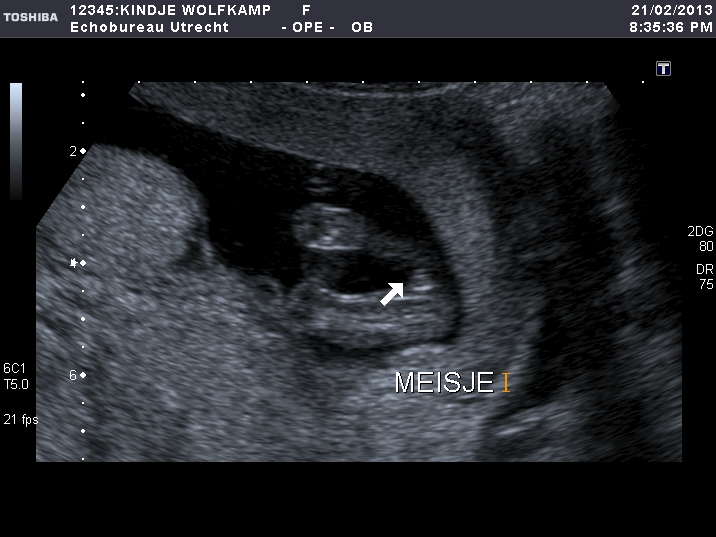

Thread updated with confirmed 15w u/s girl pictures :-)

Attachment 9168